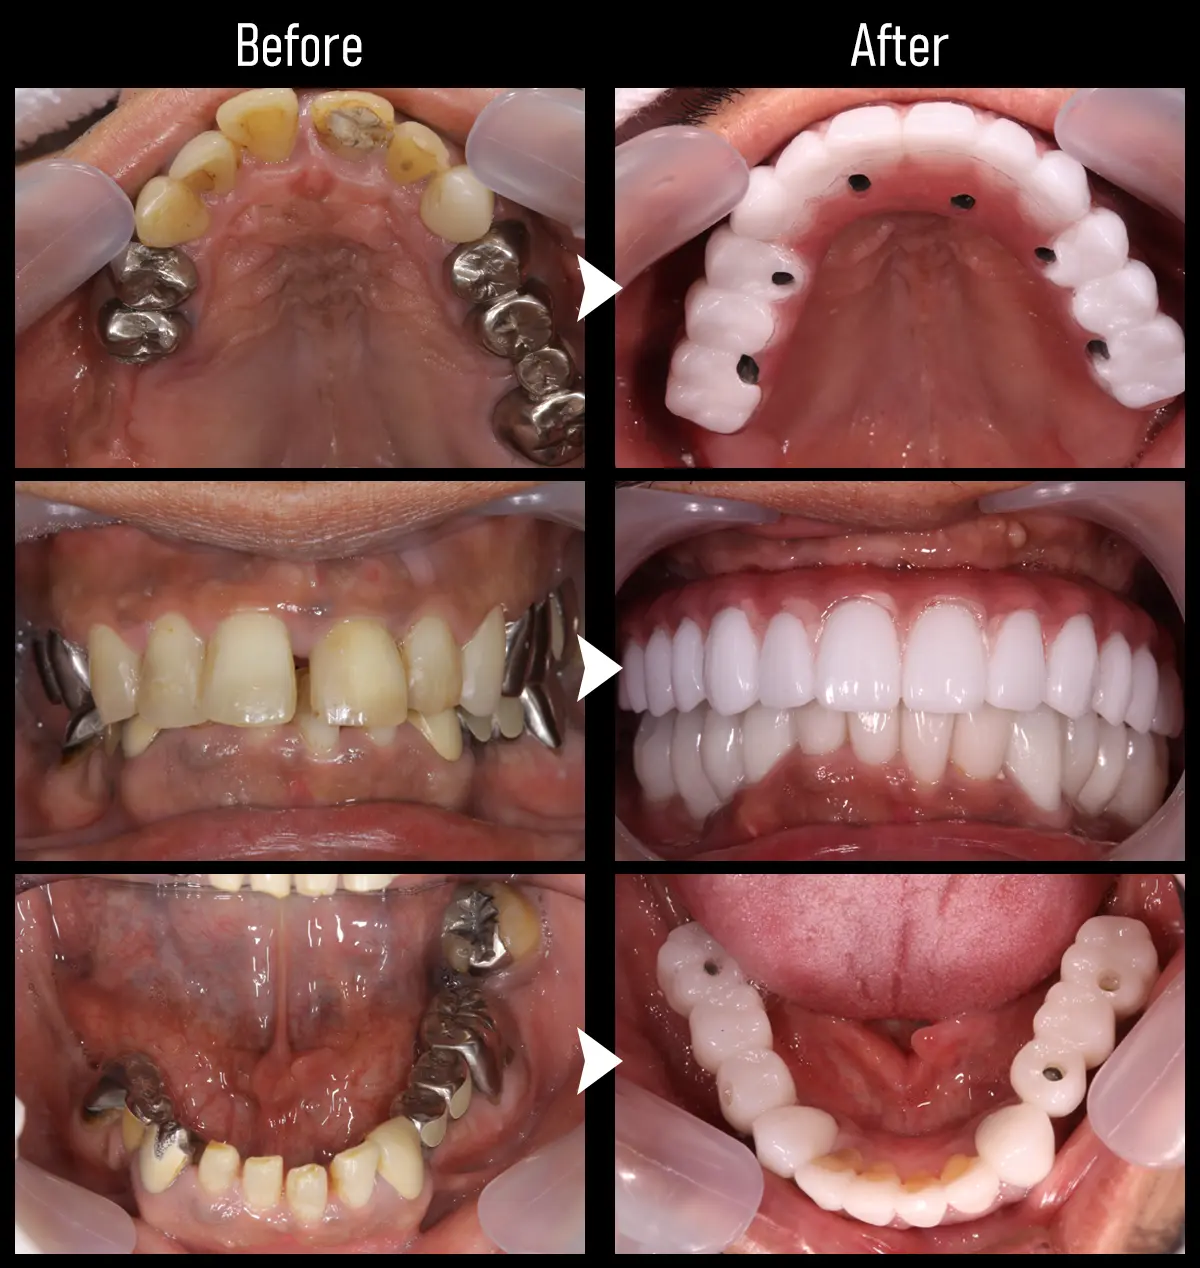

CASE:複数歯インプラント2

主訴 前歯が取れた

治療内容 上顎に4本、下顎に2本インプラント治療を行い、前歯を含め補綴治療を実施

標準費用(自費) 478.5万円